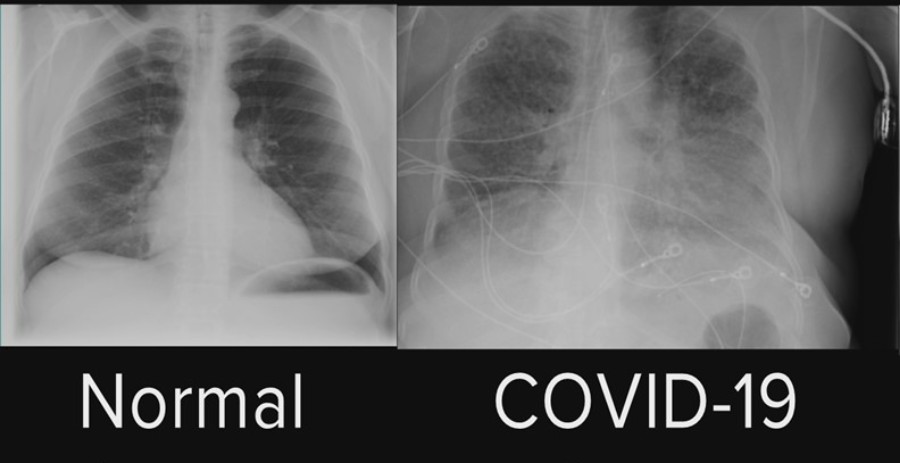

TC tórax (11/06/2020): Opacidades com atenuação em vidro fosco,

esparsamente distribuídas em ambos os pulmões, em praticamente todos

segmentos, predominantemente periféricas, com grandes focos de

consolidação esparsos.

Sinais que, embora inespecíficos, são sugestivos de processo inflamatório

pulmonar, comumente observados em COVID-19

(padrão típico na classificação RSNA)*.

Acometimento pulmonar estimado entre 35 e 55%.

HD: PNM por COVID-19 (TC tórax com acometimento de 35 a 58% do

parênquima pulmonar)